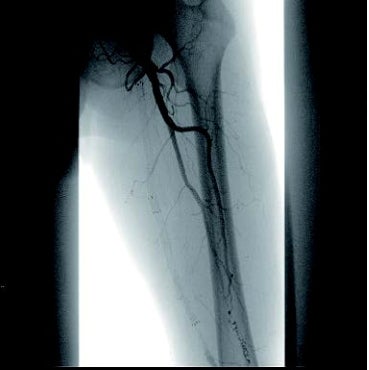

[背景] 左間欠性跛行で14年前に左SFAにベアナイチノールステント6 mm × 120 mm 2本が留置されている(図1)。約7年前に左間欠性跛行が増悪し、来院。外来での超音波検査でベアステントの完全閉塞を認めた(図2)。高度の跛行があり、再治療を実施した。